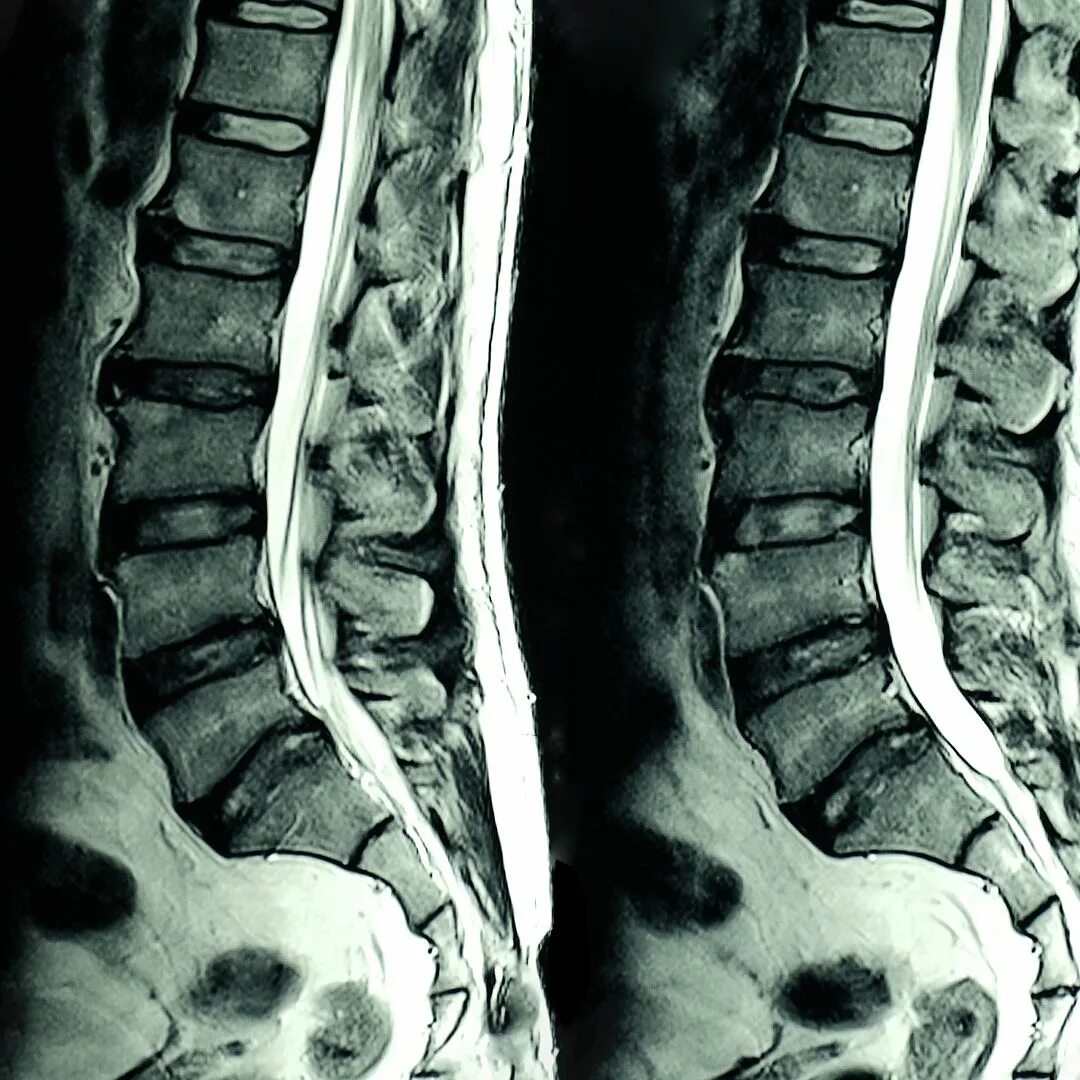

Код компрессионного перелома позвоночника